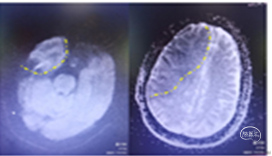

术后8小时出现意识不清,CT示脑水肿明显,给予去骨辨减压重症监护笫3天呈浅昏迷,双下肢肌力3级。第5天,病情加重,预后不良。

患者出现意识不清,病情加重。查CT左侧大脑中动脉区域水肿,低密度改变,中线移位。为大脑中动脉闭塞后改变,恶性脑水肿。

重症脑血管病管理:经甘露醇、白蛋白、3%氯化钠脱水、高压氧、依达拉奉、吡拉西坦脑保护治疗13天水肿消退,脑中线无移位,左侧大脑中动脉区域较前变淡。脑沟脑回显示清楚。